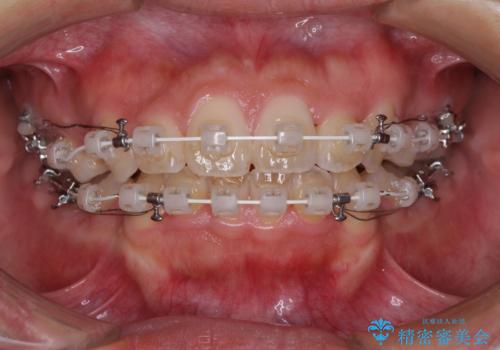

- 審美装置

- 1年4ヶ月

- 10-30回

非常にスムーズに歯列移動が行われ、当初は2-2.5年を予想していましたが、僅か1年4ヶ月で治療を終えることができました。